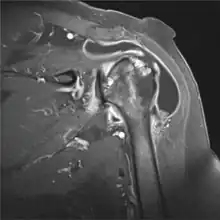

Imaging

X-rays may help visualize bone spurs, acromial anatomy and arthritis. Further, calcification in the subacromial space and rotator cuff may be revealed. Osteoarthritis of the acromioclavicular (AC) joint may co-exist and is usually demonstrated on radiographs.

MRI imagining can reveal fluid accumulation in the bursa and assess adjacent structures. In chronic cases caused by impingement tendinosis and tears in the rotator cuff may be revealed. At US, an abnormal bursa may show

- fluid distension,

- synovial proliferation, and/or

- thickening of the bursal walls.[10]

In any case, the magnitude of pathological findings does not correlate with the magnitude of the symptoms.[10]